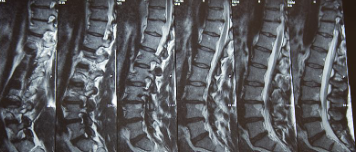

허리디스크 증상 치료방법 및 수술비용에 대해 알아보겠습니다. 허리디스크는 척추 뼈 사이에 있는 디스크가 손상되어 신경을 압박하는 질환입니다. 디스크는 척추뼈 사이의 충격을 흡수하고 척추의 움직임을 부드럽게 해주는 역할을 하는데, 이 디스크가 손상되면 신경을 압박하여 통증, 마비, 감각 이상 등의 증상이 나타납니다. 허리디스크는 흔히 40~50대 중년층에서 발생하지만, 젊은 나이에도 발생할 수 있습니다.

1. 허리 통증: 허리디스크의 주요 증상 중 하나는 허리 통증입니다. 이 통증은 영향을 받은 디스크 부위에서 발생하며 둔한 통증, 날카로운 통증 또는 지속적인 불편감으로 나타날 수 있습니다. 통증의 강도는 다양할 수 있으며 영향을 받은 디스크에 압력을 가하는 움직임으로 악화될 수 있습니다.

2. 방사통: 허리디스크는 방사통을 유발할 수 있습니다. 이 통증은 일반적으로 영향을 받은 신경의 경로를 따라 엉덩이, 허벅지, 다리로 이동합니다. 통증은 해당 부위의 따끔거림, 무감각 또는 바늘로 찌르는 듯한 감각을 동반할 수 있습니다.